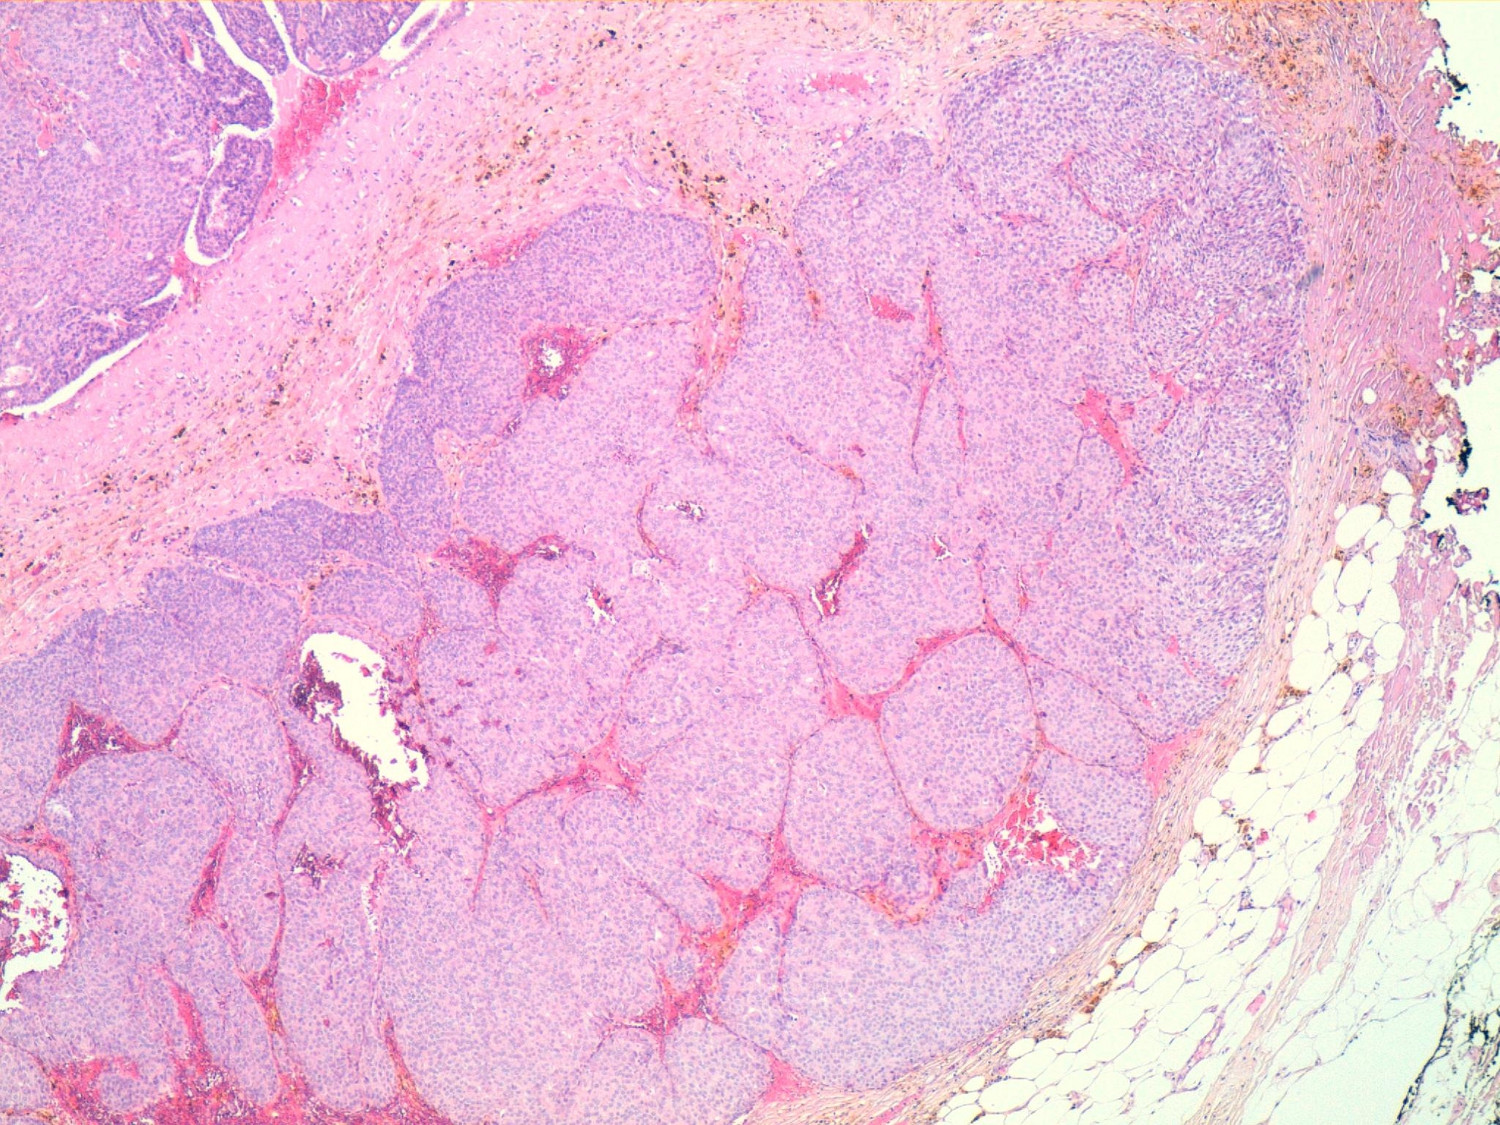

The pathological diagnosis was of a solid papillary intracystic carcinoma with a point of invasion - infiltrating papillary carcinoma and intracystic papillary carcinoma (Fig. 4).

Figure 4

Nests with solid papillary growth pattern. HEx40 technique